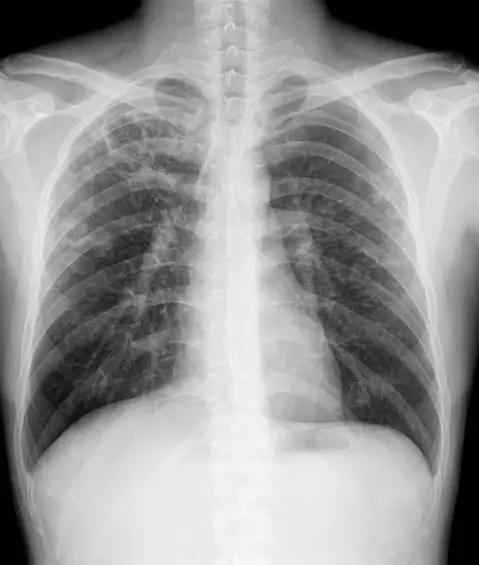

30歲男性因咳嗽有痰數月而就醫,其胸部X光檢查如附圖。下列何者為最可能的診斷?

- 影像為PA投影胸片,穿透度適中,左右肺野及中縱隔結構清晰。

- (患者左側)上葉可見多發、不規則厚壁空洞性病灶,壁緣粗糙;空洞內無顯著液平面。

- 同側縱隔略向病灶側牽拉偏移,橫膈輕微抬高,顯示纖維化引起的肺容積減少。

- 對側肺野呈代償性過充氣狀態,肺紋理較為增粗。

- 未見大範圍實變或明顯胸腔積水,也無胸腔氣胸徵象。